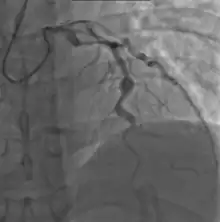

Angiography showing ectatic LAD, with largest aneurysm = 6.5 mm in diameter

Heart complications are the most important aspect of Kawasaki disease, which is the leading cause of heart disease acquired in childhood in the United States and Japan.[32] In developed nations, it appears to have replaced acute rheumatic fever as the most common cause of acquired heart disease in children.[16] Coronary artery aneurysms occur as a sequela of the vasculitis in 20–25% of untreated children.[53] It is first detected at a mean of 10 days of illness and the peak frequency of coronary artery dilation or aneurysms occurs within four weeks of onset.[49] Aneurysms are classified into small (internal diameter of vessel wall <5 mm), medium (diameter ranging from 5–8 mm), and giant (diameter > 8 mm).[32] Saccular and fusiform aneurysms usually develop between 18 and 25 days after the onset of illness.[16]